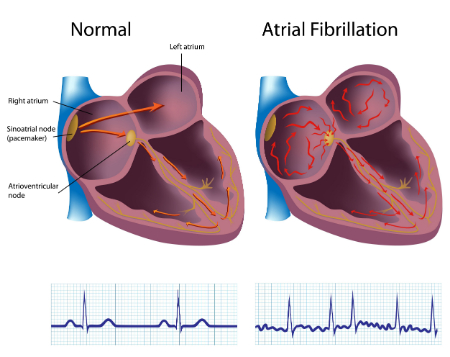

بزرگشدگی دهلیز چپ میتواند مشکلات پزشکی مانند آریتمی یا ریتمهای غیرطبیعی قلب ایجاد کند. این موارد شامل علائمی مانند:

• تپش قلب

• لرزش قفسه سینه

• درد قفسه سینه

• غش کردن

• فیبریلاسیون دهلیزی

بله، میتواند منجر به آریتمی (مثل فیبریلاسیون دهلیزی) و احساس تپش یا لرزش در قفسه سینه شود.